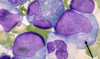

Erythroid Precursors in

MyeloDysplastic Syndrome (MDS)

[Nuclear BIMS - Budding / irregularities / multinucleation / separation of lobes]